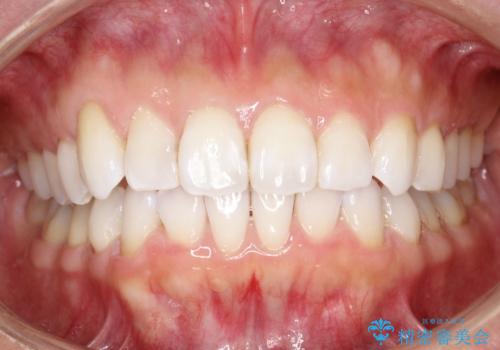

抜歯せずに八重歯のマウスピース矯正

- 非抜歯・遠心移動+IPR+拡大 によるマウスピース矯正を計画した。

八重歯がシビアな場合、抜歯をしないと治せないケースもありますが、奥歯の位置関係を修正したり、歯のサイズダウンを行うことで、抜歯をせずに改善できる場合もたくさんあります。